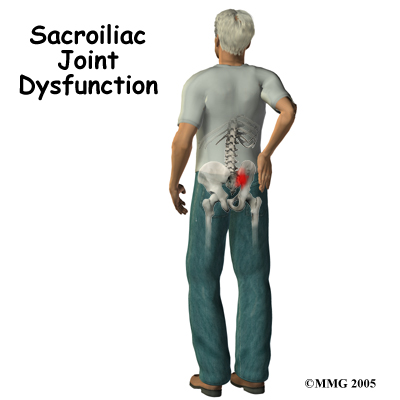

A painful Sacroiliac (SI) joint is one of the more common causes of mechanical low back pain. A ‘dysfunction’ of the SI joint is a term that is used to describe the pain associated with this joint because it is often still unclear why this joint becomes painful and leads to low back pain. Most people who suffer from this problem can reduce the pain with physical therapy treatment and manage the problem.

At the lower end of the spine, just below the lumbar spine lies the sacrum. The sacrum is a triangular shaped bone that is actually formed by the fusion of several vertebrae during development. The SI joint sits between the sacrum and the iliac bone (thus the name “sacroiliac” joint). On many patients you can identify these joints from the outside as two small dimples on each side of the lower back at the belt line.

Most commonly the pain from an SI joint dysfunction is either directly over the SI joint itself or may radiate pain lower down into the buttocks. The pain may affect one side or both SI joints. Most times the pain from an irritable SI joint remains well above the knee, but in a few cases it can radiate down the leg all the way to the foot and may be confused with a herniated disc of the lumbar spine. The pain may also radiate into the groin area. People often feel muscle spasm or tightness in one or both of their buttocks muscles when the SI joint is affected.

Most commonly the pain from an SI joint dysfunction is either directly over the SI joint itself or may radiate pain lower down into the buttocks. The pain may affect one side or both SI joints. Most times the pain from an irritable SI joint remains well above the knee, but in a few cases it can radiate down the leg all the way to the foot and may be confused with a herniated disc of the lumbar spine. The pain may also radiate into the groin area. People often feel muscle spasm or tightness in one or both of their buttocks muscles when the SI joint is affected.